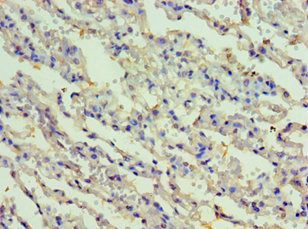

Immunohistochemistry of paraffin-embedded human lung tissue using CSB-PA897497ESR1HU at dilution of 1:100